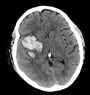

The Alberta Stroke Program Early CT Score is a semiquantitative method for acute ischemic stroke CT scoring within the MCA territory. It was designed to simplify noncontrast CT assessment by dividing the affected vascular territory into 10 predefined regions and subtracting points for early ischemic abnormalities. Typical findings include parenchymal hypoattenuation and loss of gray-white differentiation, which may be subtle during the hyperacute phase.

The method is straightforward. Begin with a score of 10 on the affected side and subtract 1 point for each region that demonstrates early ischemic change. A score of 10 indicates no visible ischemic abnormality in the scored MCA regions on baseline CT, whereas a score of 0 indicates diffuse involvement across all 10 regions.

ASPECTS on Noncontrast CT in Acute Ischemic Stroke

For radiologists, the main challenge is not the arithmetic but the image interpretation. Early ischemic changes can be faint, especially in the insula, deep gray nuclei, and posterior cortical MCA regions. Reader experience affects performance, and interobserver variability remains a known limitation of CT ASPECTS. Published studies have shown that agreement can range from moderate to substantial, depending on reader expertise, region assessed, and how the score is grouped for treatment decisions [1][4][5].

Some investigators have reported improved interobserver agreement with narrower CT window settings, including 8 HU width and 32 HU center, compared with more conventional settings [5]. In practice, window adjustment can be helpful when searching for subtle hypoattenuation, but final interpretation still depends on the full imaging context, side-to-side comparison, and experience with acute stroke imaging evaluation.